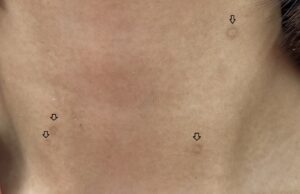

目周りの色素沈着でお悩みではありませんか??東京の美容皮膚科・外科お茶の水美容形成クリニック。

目の周りの色素沈着を治したい!黒ずむ原因から治療法までを徹底解説ハダメディア by BIHADADO.TOKYO。